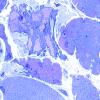

Pompe Disease (3)